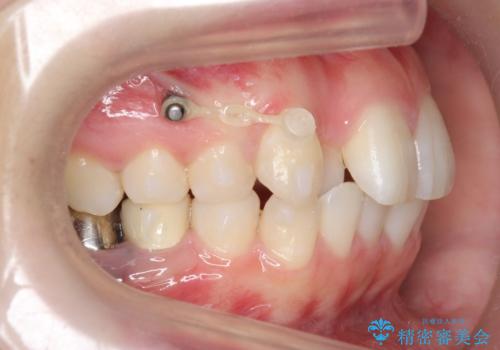

左上の犬歯が歯肉退縮しており、そこを抜歯して矯正することにしました。

右上については、奥歯をインプラント矯正により後ろに動かして、引っ込んだ前歯を並べるスペースを確保しました。

右下6番については保存不可能であり、矯正治療終了後にインプラント補綴しています。